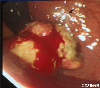

A case of amelanotic melanoma of the rectum.

Endoscopy

Malignant melanoma/